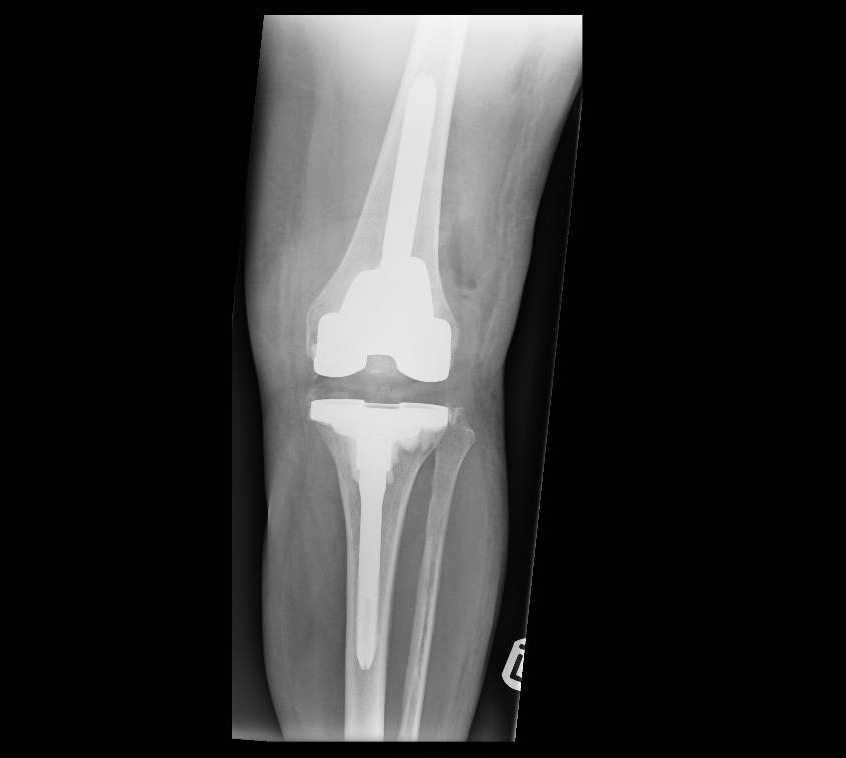

Revision Knee Surgery

Persistent, worsening pain in a knee replacement is often a sign that it is failing. It is important to determine why this is happening. The three most common causes for failure of a knee replacement are that an infection has developed, there is malalignment of the prosthesis or that it has loosened from the bone. It is vitally important to investigate for the cause of failure, this often includes blood tests, X-rays, a bone scan and fluid samples from the joint.

Performing reconstruction surgery to recreate a well-functioning knee replacement is technically demanding and requires expertise from a surgeon who regularly performs these operations. I regularly perform this surgery and use advanced surgical techniques and specialised bone restoration methods.

Generally, bone cement is used to fix a total knee replacement to the bone, in some cases where an uncemented knee replacement is used the host bone grows onto the implant. If this interface between the bone and the cement or the bone and the implant (in an uncemented knee) fails then the implant will loosen and will result in progressive pain. Usually loosening occurs many years after surgery, if it occurs early on it is often due to a technical problem during the implantation surgery.

Another cause of loosening can be a wearing out of the plastic insert that sits between the metal implants of the femur and tibia. These wear particles that are generated can cause quite extensive bone loss around the implant and this significantly increases the complexity of the surgery.

It is therefore important that your surgeon has a range of options available to him to reconstruct the knee after a failed knee replacement. This may include advanced surgical approaches, use of complex revision implants including custom made implants, use of bone graft or trabecular metal implants to reconstitute lost bone.